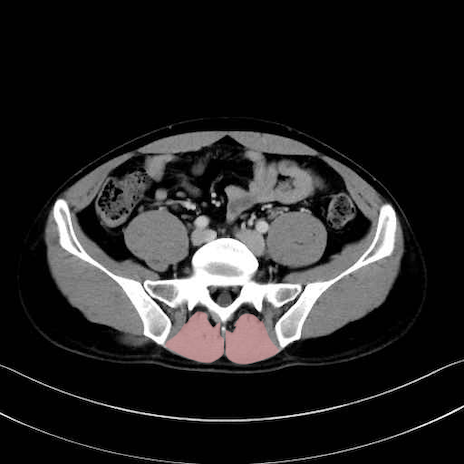

肛門挙筋 (Levator ani)